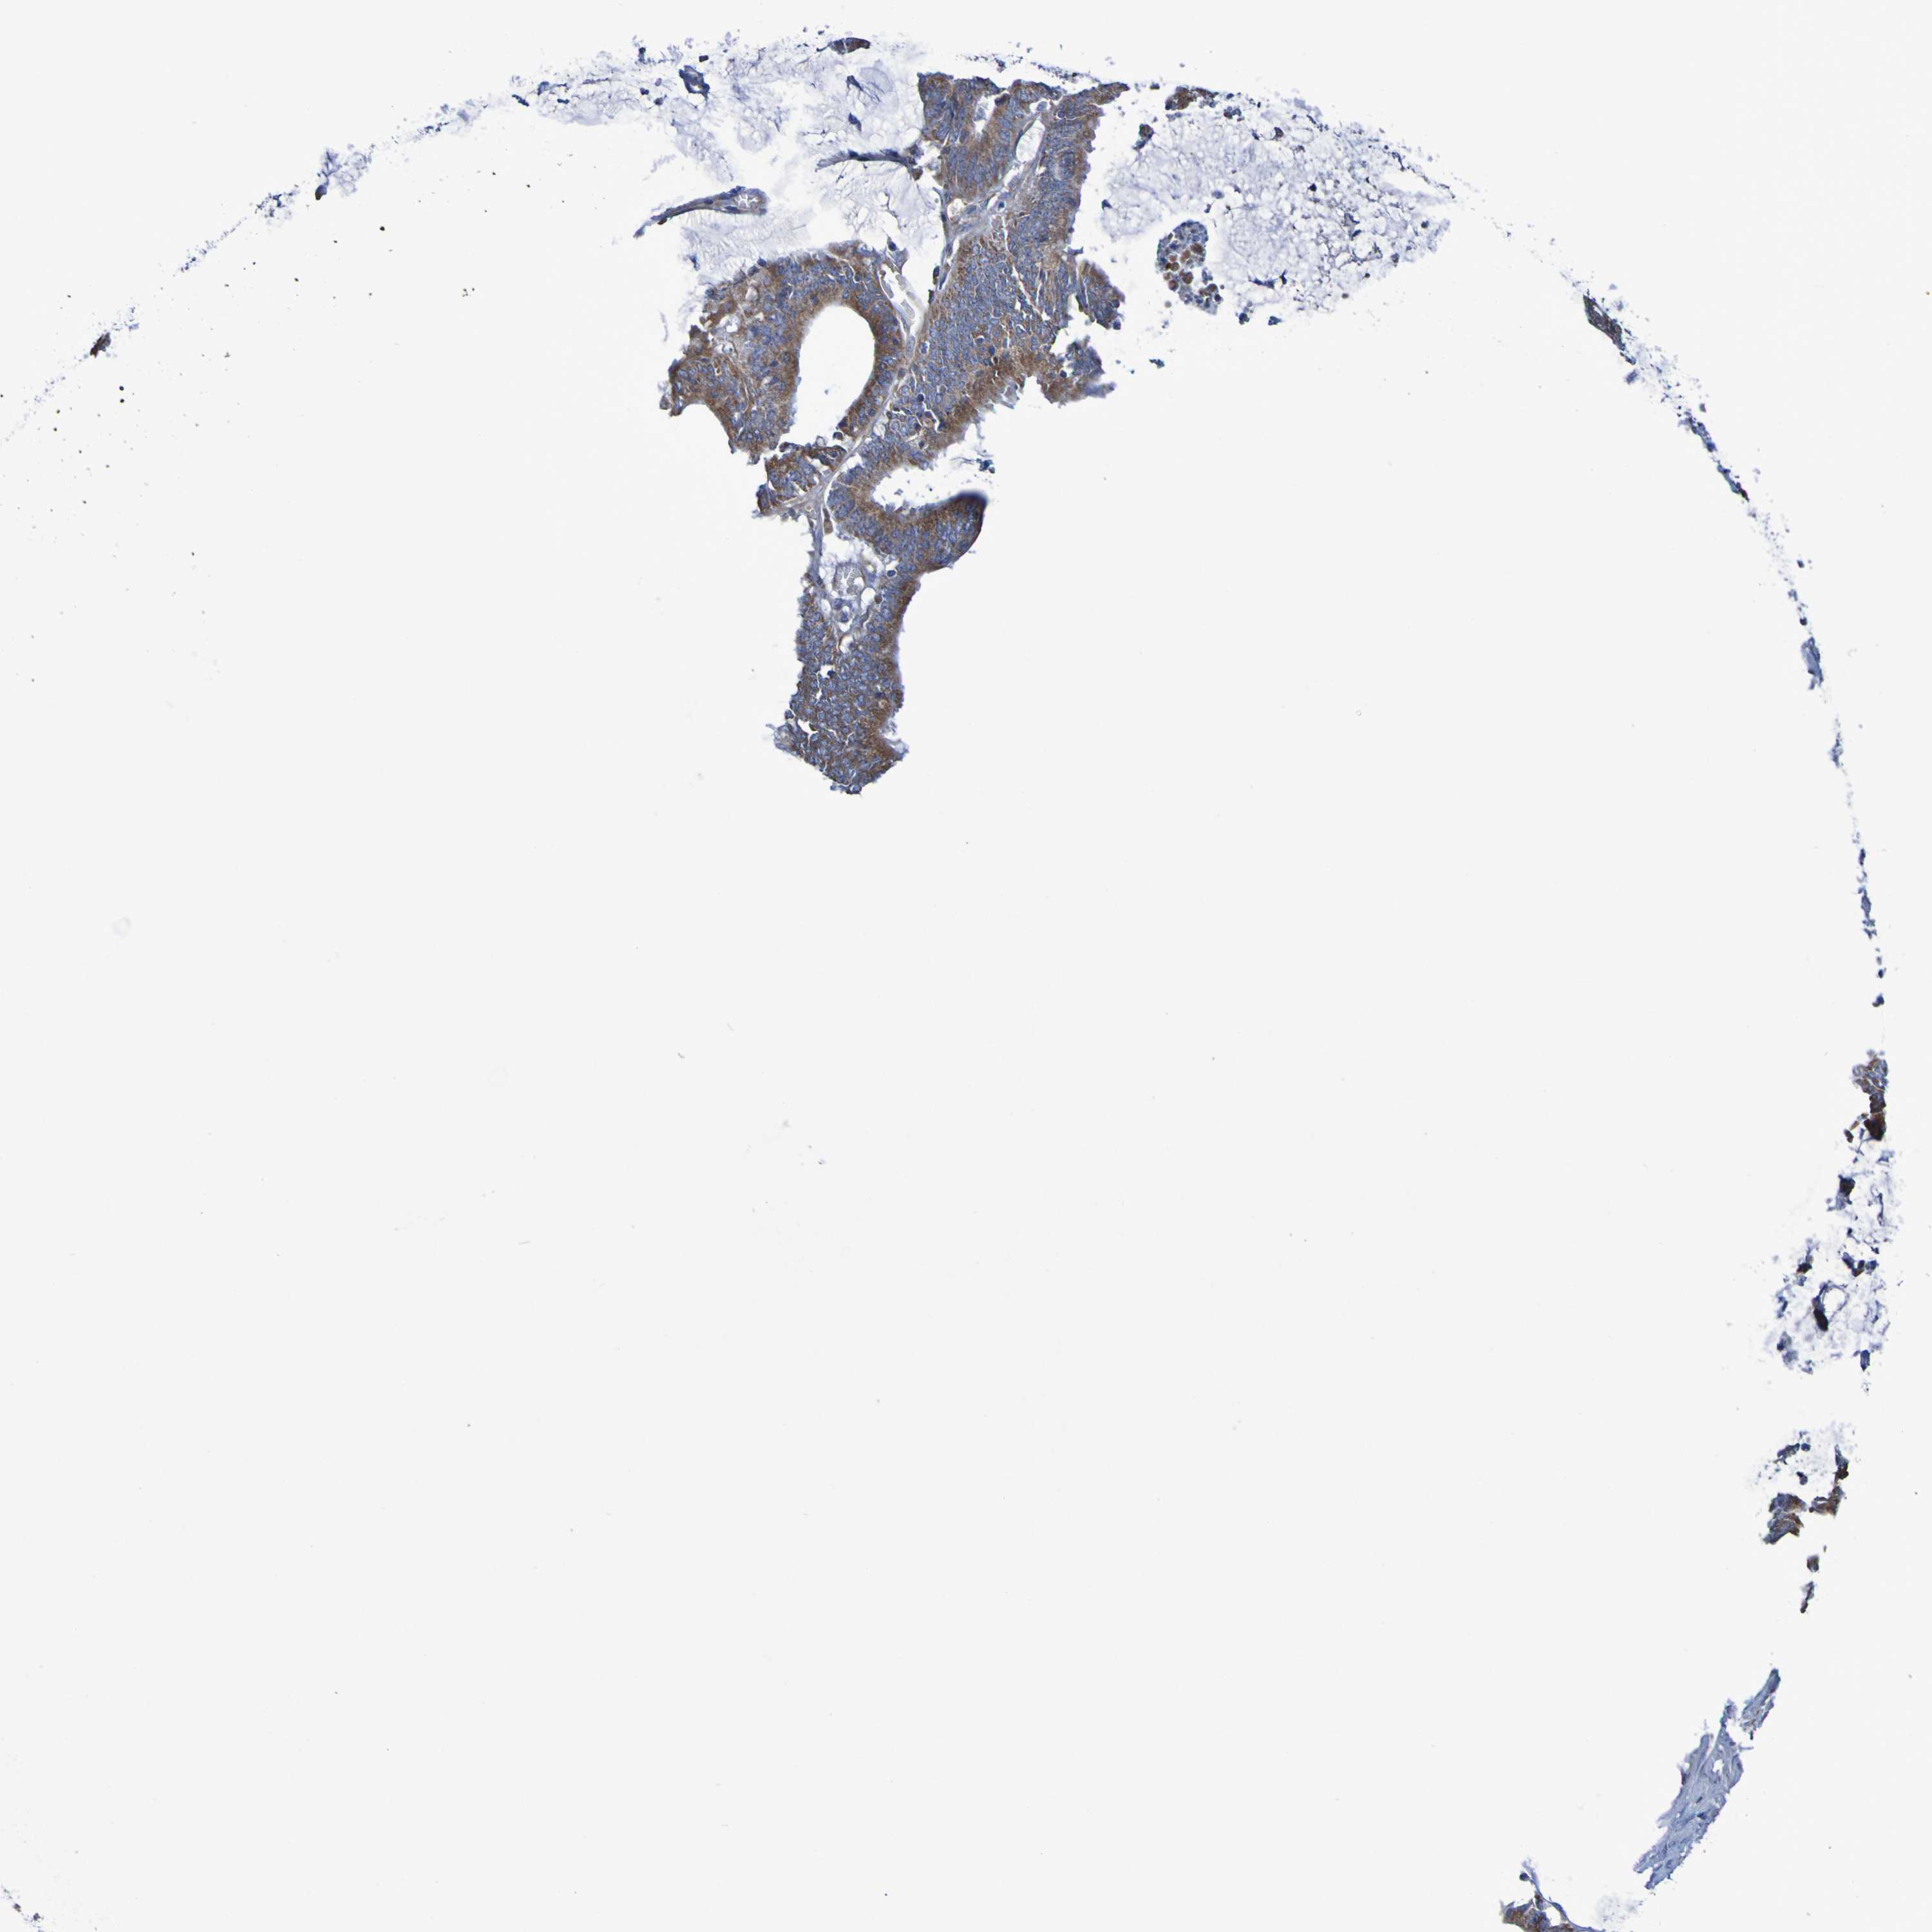

CANCER COLORECTAL CANCER Show tissue menu

Colorectal cancer

Human cancer

Colon adenocarcinoma